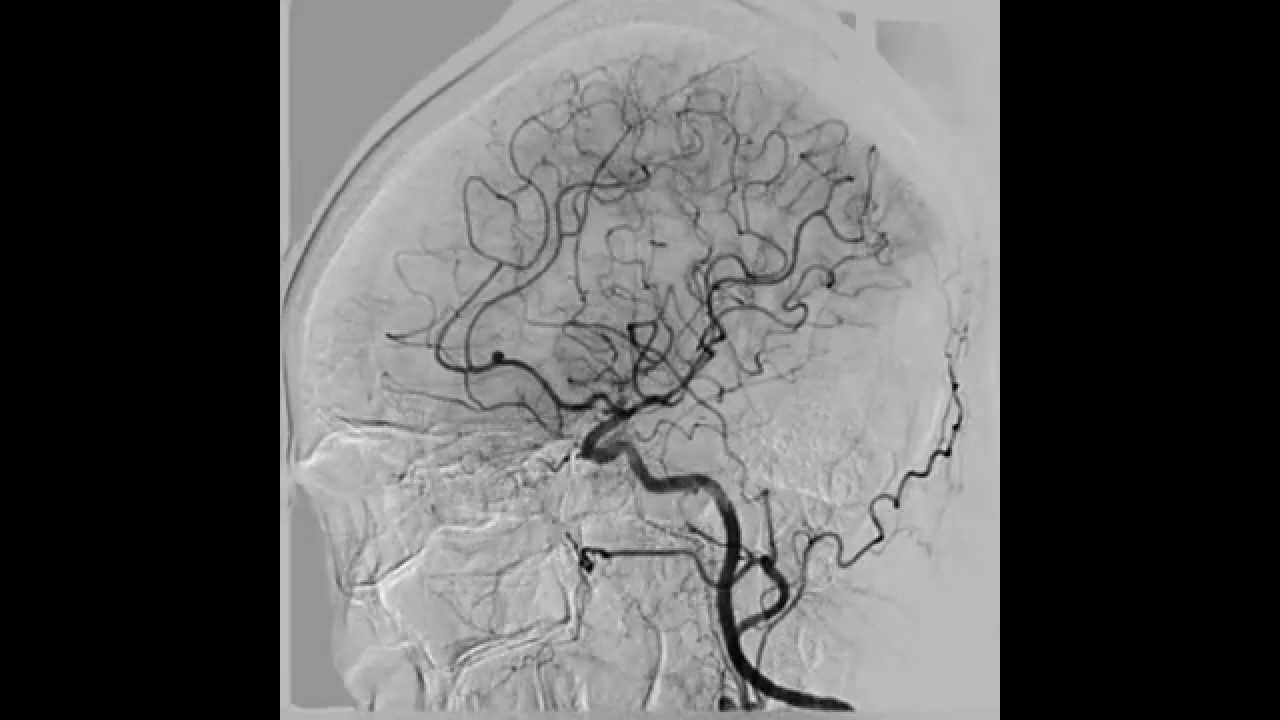

Сегмент м1 сма

Сегмент м1 сма 109 фото